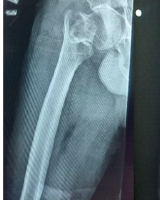

A 25-year-old male with a history of left medial malleolar fracture, previously fixed with two screws in February 2025, presented to the Emergency Department 5 months later following a motorcycle accident that resulted in a new bimalleolar fracture of the left ankle. On examination, there was moderate swelling and a limited range of motion (ROM) of the left ankle. Distal neurovascular status was intact, and all compartments were soft. A superficial abrasion was noted over the medial aspect of the left foot. An X-ray of the left ankle revealed a bimalleolar fracture along with non-union of the medial malleolar fracture (Fig. 1).

Figure 1: Pre-operative anteroposterior (a and b) and lateral (c) X-rays of the left ankle showing a bimalleolar fracture and bent medial malleolar screws with fracture non-union from previous fixation.